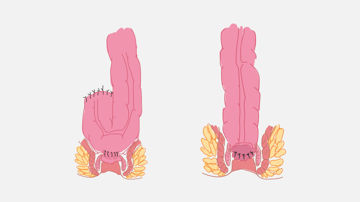

Prolaps bedeutet "aus dem Platz fallen". Ein Beckenorganprolaps (BOP) tritt auf, wenn die Scheidenwände, die Gebärmutter oder beides ihre normale Unterstützung verlieren und verrutschen. Andere nahe gelegene Beckenorgane, wie die Blase oder der Darm, können betroffen sein und ebenfalls aus ihrer normalen Position im Körper "vorfallen". Die Zystozele ist die häufigste Art von BOP.

Eine Rektozele ist eine Ausbuchtung in der vorderen oder hinteren Rektumwand, in der sich Stuhl sammeln kann, was zu einer unvollständigen Entleerung führt. In diesem Artikel erfahren Sie mehr über diese häufige Erkrankung.